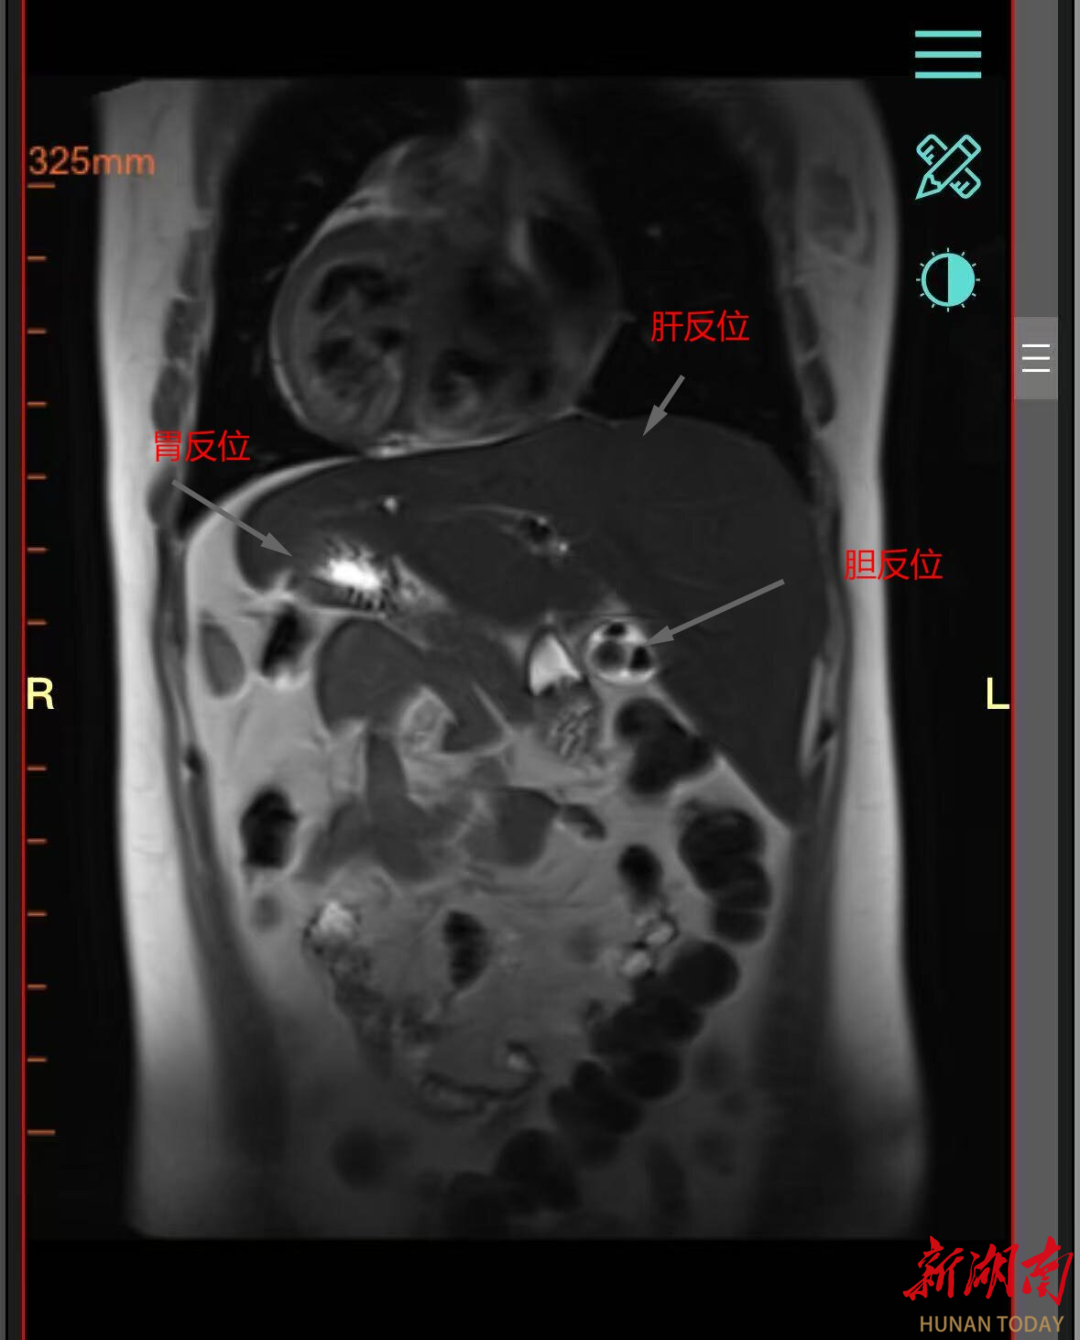

32岁的王女士近两年反复上腹疼痛,到岳阳市中医医院检查后得知困扰她的正是胆囊结石合并胆囊炎。这本是一个外科常见病,但入院前王女士体检显示,王女士是一名全内脏反位患者。简单来说就是她的心脏、肝脏、胃、胆囊等所有胸腔腹腔器官的位置,与正常人完全相反,如同镜中影像。对一般人来说,胆囊切除是个常规手术,但对王女士而言,却变得异常复杂——因为她的胆囊不在右边,而在左边。这无疑大大增加了诊断的复杂性和手术的风险与难度,许多医院对此类手术倍感棘手。

首先,医学影像科为王女士做了详细CT和MRI检查,将王女士的“镜面”内脏绘制了一幅极其精确的“倒置地图”,清晰展现了反位器官的形态、血管走行、胆道结构关系,为手术路径提供了至关重要的导航。